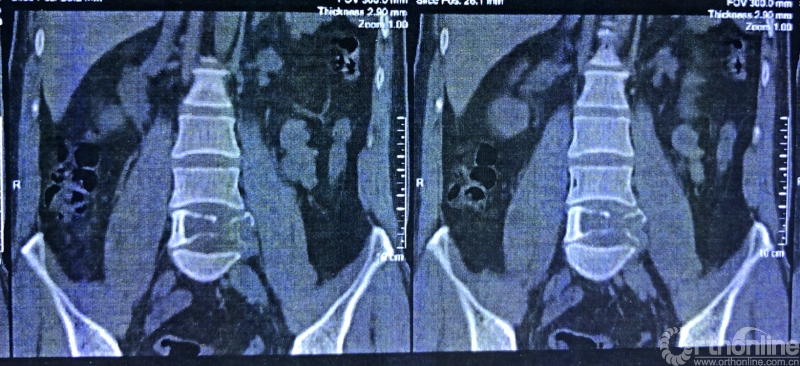

术前CT三维重建